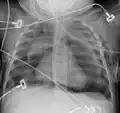

Pneumomediastinum is uncommon and occurs when air leaks into the mediastinum. The diagnosis can be confirmed via chest X-ray showing a radiolucent outline around the heart and mediastinum or via CT scanning of the thorax.

Pneumomediastinum and right sided pneumothorax post first rib fracture in a mountain biking accident. -